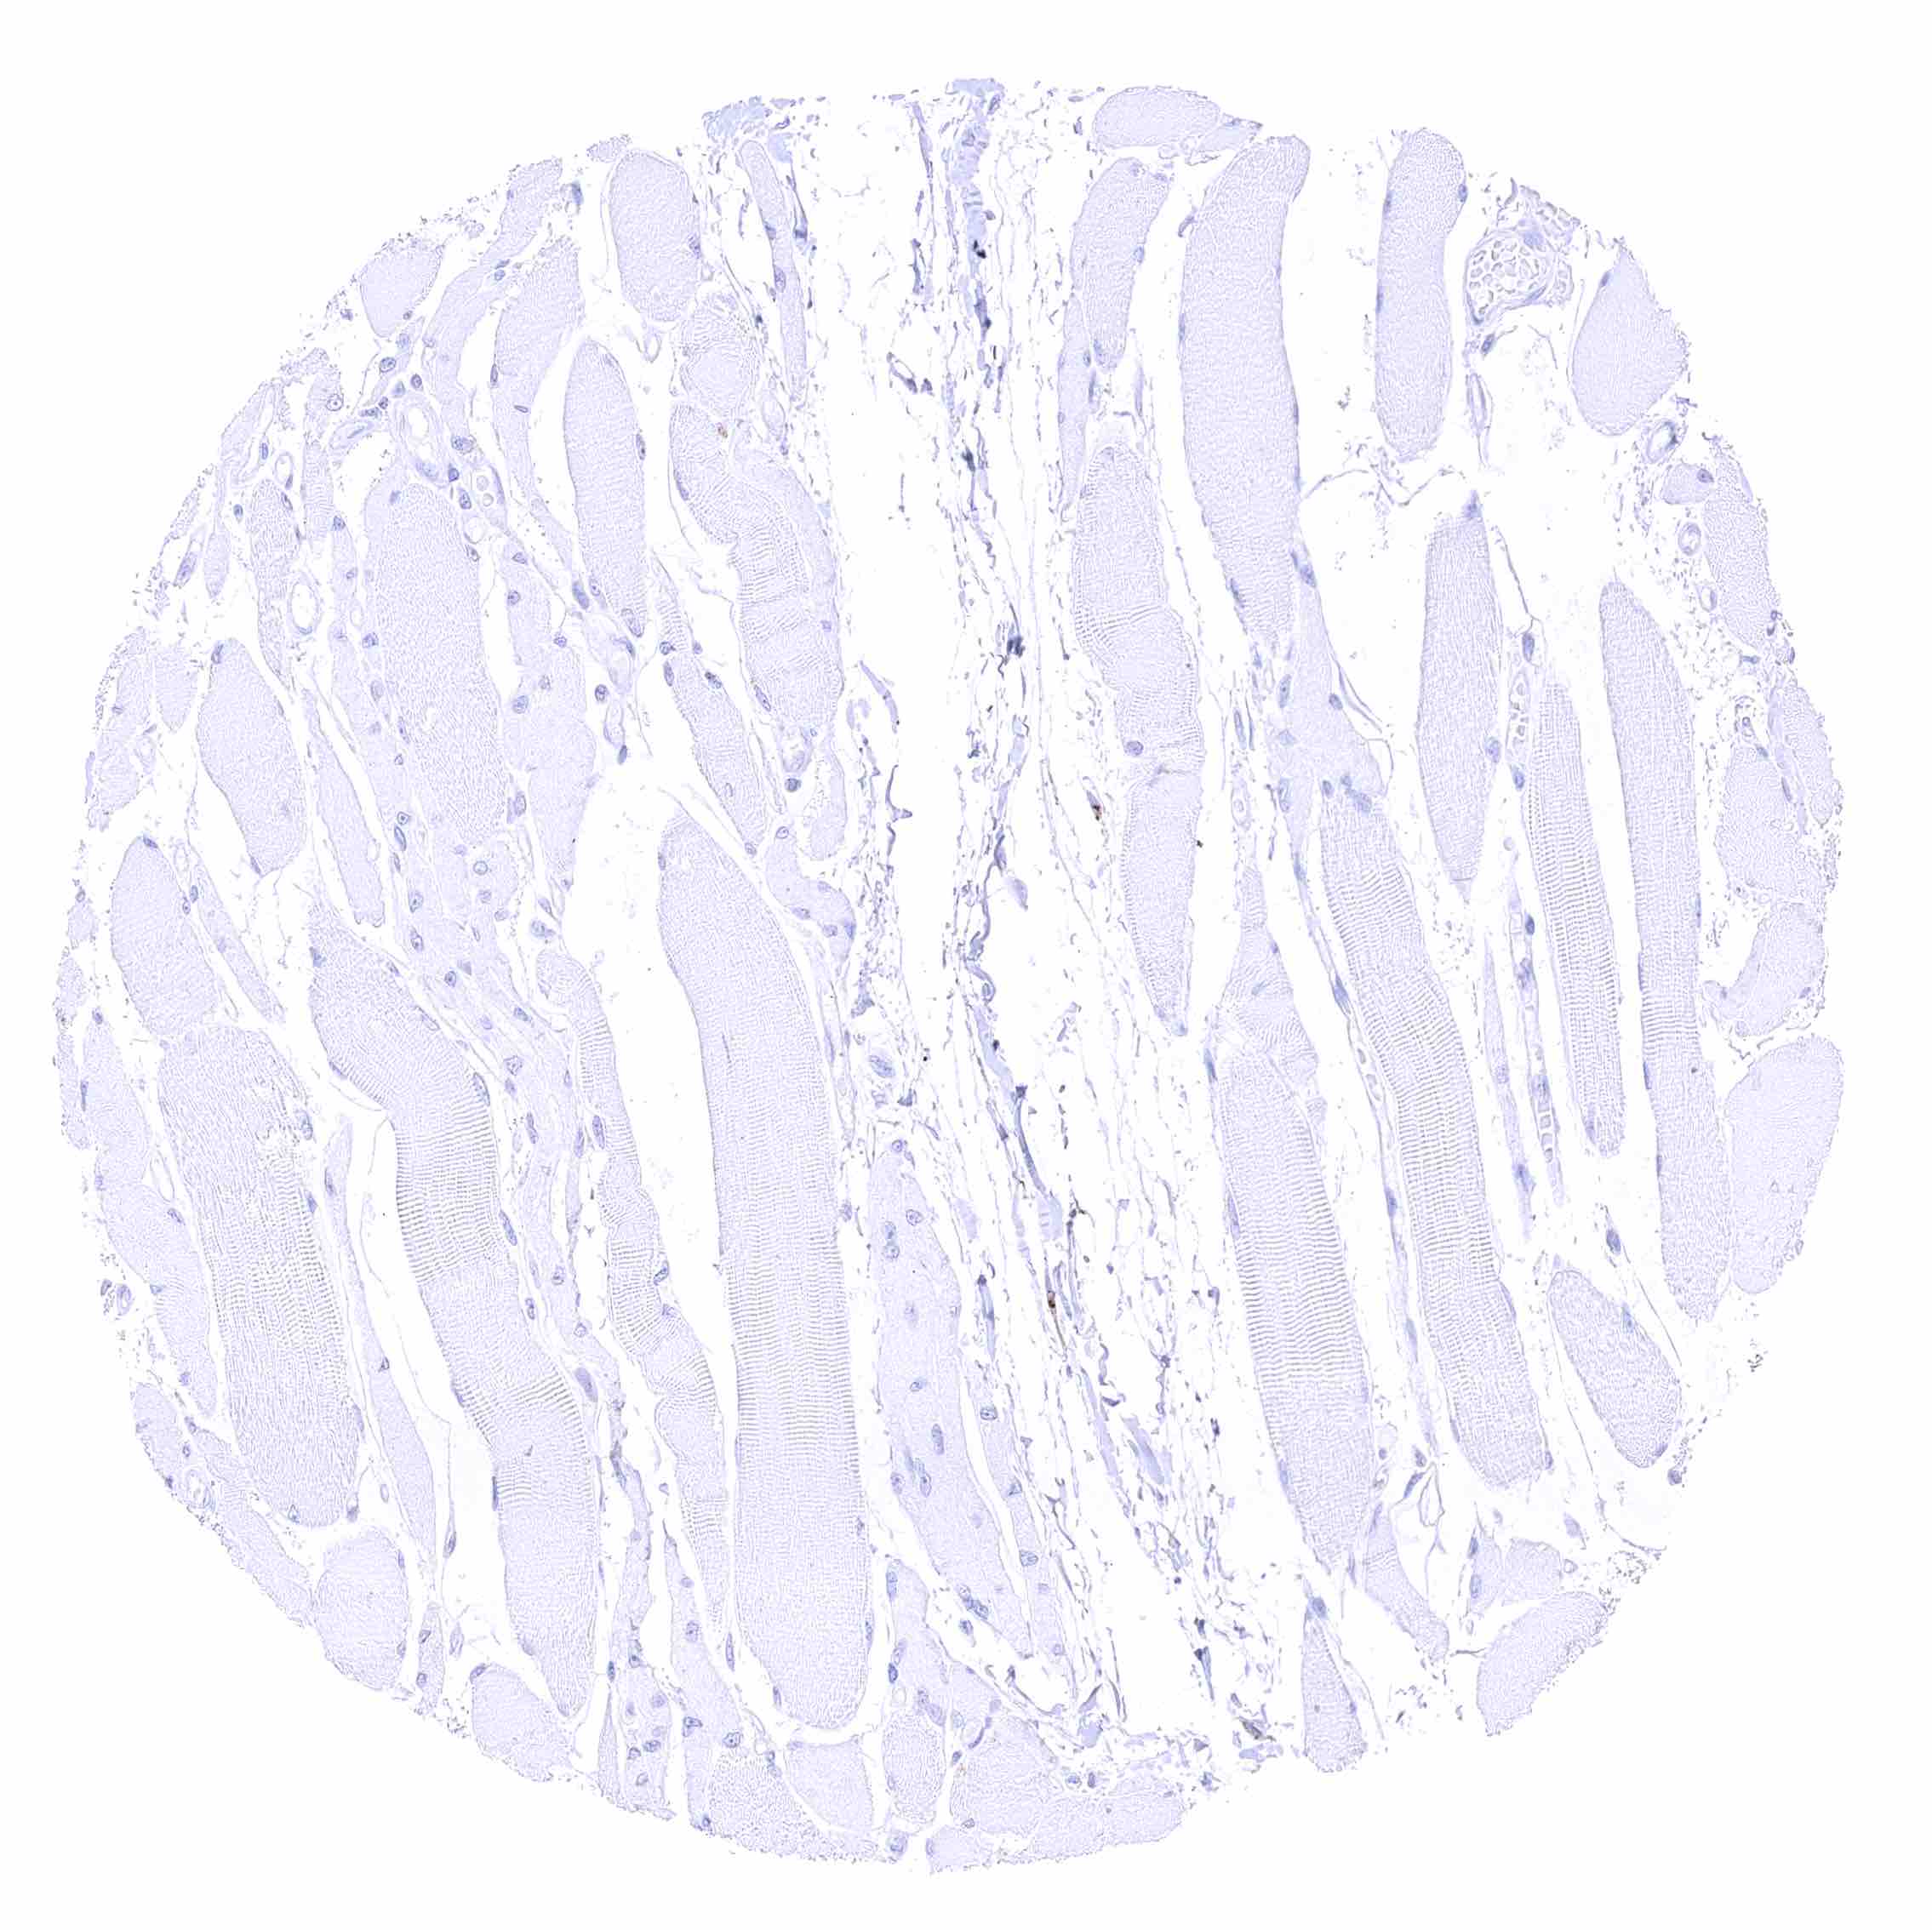

| Muscle/connective tissue | Heart muscle | Negative. |

| Skeletal muscle | Negative. | |

| Smooth muscle | Negative. | |

| Vessel walls | Negative. | |